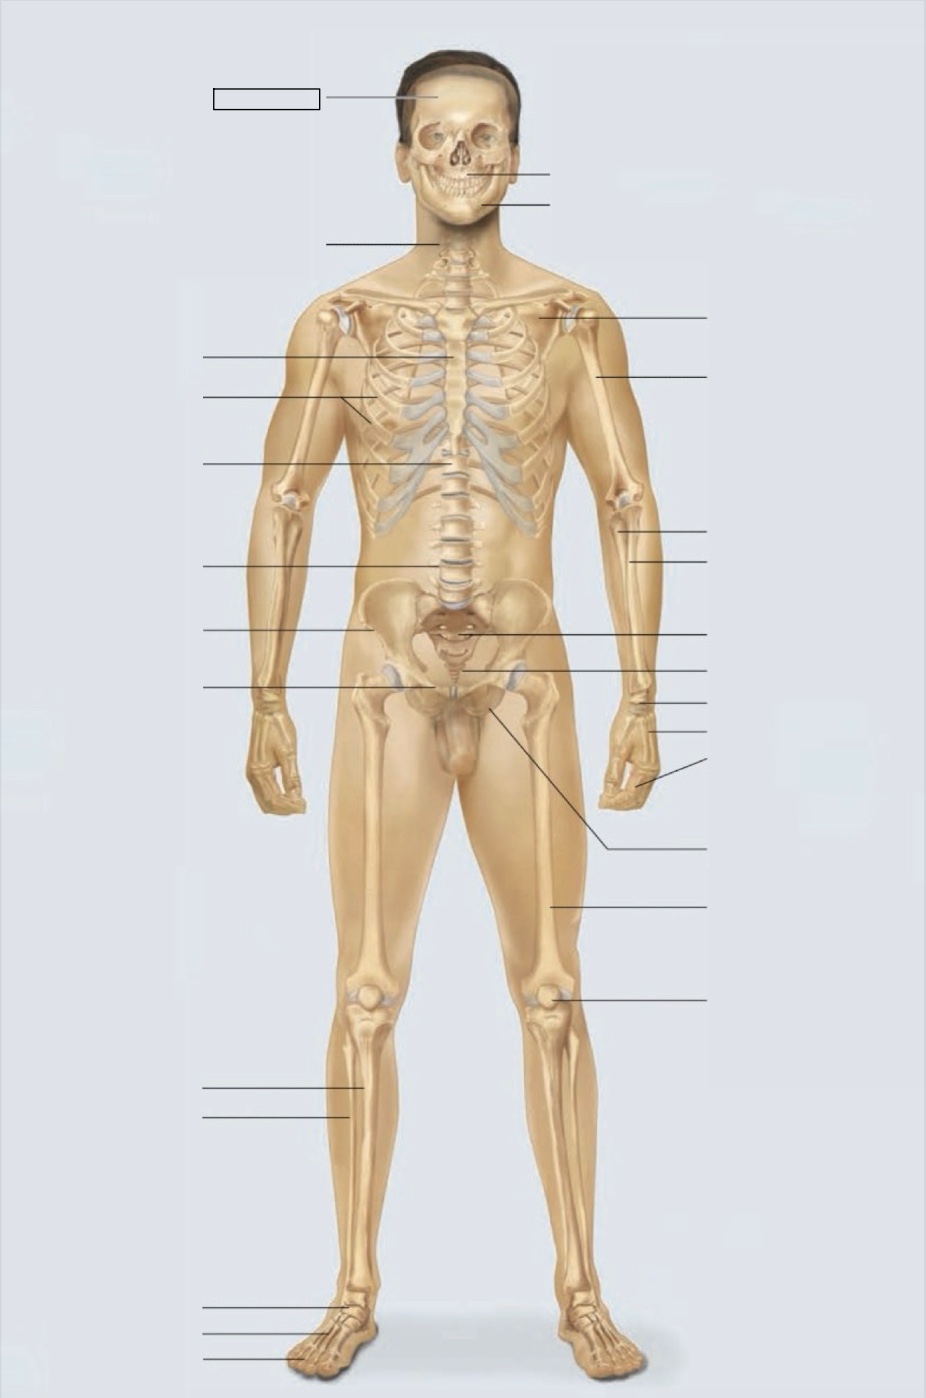

maxilla

mandible

scapula

humerus

ulna

radius

sacrum

coccyx

carpals

metacarpals

phalanges

ischium

femur

patella

phalanges

metatarsals

tarsals

fibula

tibia

pubis

ilium

lumbar vertebrae (L4)

thoracic vertebrae (T11)

ribs

sternum

cervical vertebrae

skull